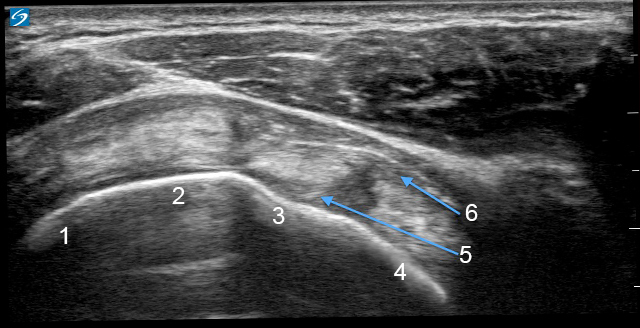

Shoulder Rotator Cuff Interval Image

1. Infraspinatus

2. Supraspinatus

3. Biceps Tendon (BT)

4. Subscapularis

5. Superior Glenohumeral Ligament (SGHL)

6. Coracohumeral Ligament (CHL)